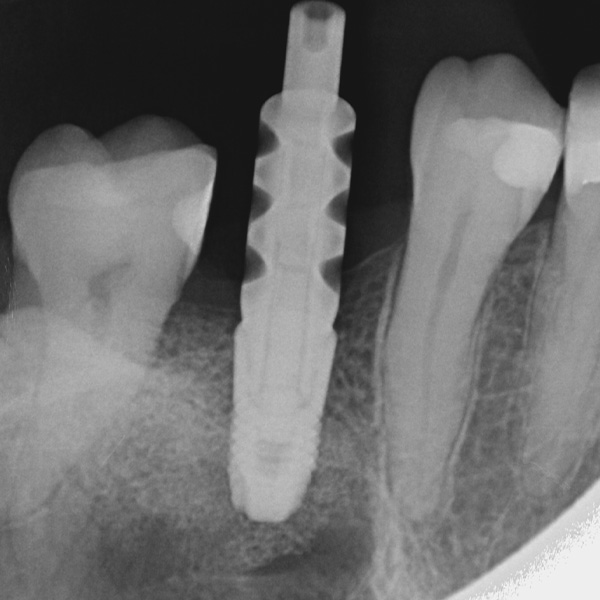

Restorations and implants are exposed to especially high loads. After extraction and implantation, the patient lacks the elastic fiber apparatus of the natural dental bed. As a result, chewing forces are not absorbed, but transmitted directly to the restoration, the implant, the bone and the opposing dentition. The hybrid ceramic VITA ENAMIC provides a dual network structure of ceramic (86 wt%) and polymer (14 wt%). This results in a dentin-like elasticity and the ability to absorb chewing forces. Due to its high vertical dimension, the polychrome blank VITA ENAMIC multiColor in the EMC-16 geometry enables the production of one-piece, monolithic abutment crowns, even with atrophied bone. In the following article, dentist Professor Dr. Alexander Hassel demonstrates how he provides a patient with this type of restoration.